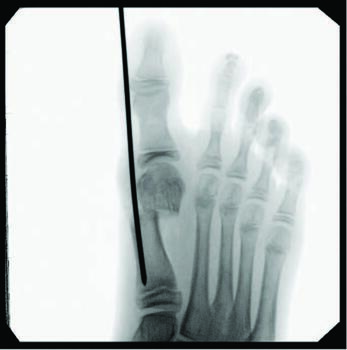

Although minimally invasive hallux valgus surgery is a more modern technique, especially for the pediatric population, it still relies, in my experience, on AO principles of fracture fixation, including anatomic reduction in the first intermetatarsal and hallux abductus angles, stable fixation, preservation of blood supply, and early active mobilization. I find the percutaneous approach allows the reduction of a wide range of mild to severe radiographic angles and preservation of blood supply. In a study of minimally invasive bunion procedures, surgeons achieved up to a 12.5 degree correction of the first intermetatarsal angle and reported a 5.3 percent reoperation rate. The study was from a surgeon’s first 94 MICA procedures, and the author challenged the previously reported steep learning curve, citing low complication rates and ease of reproducibility.13

Kaufmann and colleagues compared five-year outcomes of open distal metatarsal chevron osteotomies to a minimally invasive approach, finding comparable satisfaction as well as radiographic and clinical outcomes in both groups.16 More recently, Neufeld and team reported that the minimally invasive chevron and Akin (MICA) procedure achieves reproducible significant correction and high patient satisfaction with early weight-bearing and fast pain score improvement.13 They noted a 5.3 percent reoperation rate due to hardware removal, debridement, and neurolysis, finding no significant increase in nerve injury between the MICA and open procedure groups. The authors also noted significant deformity correction is possible with the third-generation approach of utilizing two bicortical screws.13

Over the last decade, I, the senior author, have performed hundreds of bunion procedures through both traditional and minimally invasive approaches. My criteria for surgical candidacy for MIS procedures started in the high-risk wound population with multiple comorbidities, including patients with diabetes, human immunodeficiency virus (HIV), acquired immunodeficiency syndrome (AIDS), rheumatoid arthritis (RA), and transplant recipients. All of these populations of patients are at higher risk for surgical complications, such as infections and wound and bone healing delays. My outcomes and results in these patients were so remarkable that I then expanded my criteria to include healthier and higher-demand populations, including children and athletes. In my experience, this surgical approach can help address a complex deformity in the young population, decreases postoperative rehabilitation, improves function, and avoids disrupting a child’s open growth plate. All possible without leaving hardware behind.